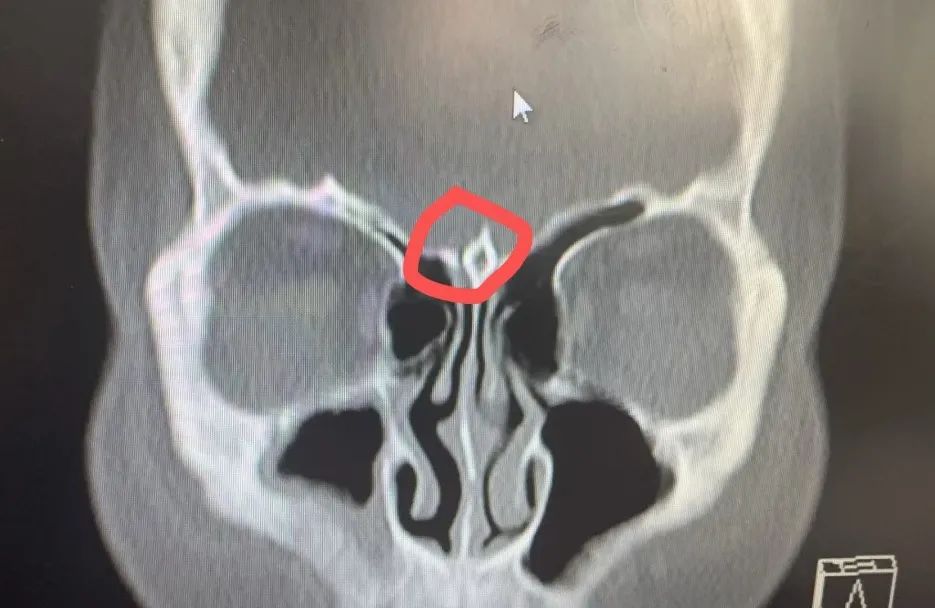

经过充分的术前准备,耳鼻咽喉头颈外科陆训彪主任带领团队为患者实施了经鼻内镜脑脊液鼻漏修补术,术中发现嗅裂顶部存在约2mm大小的白色略透明的膜状膨出物,考虑脑膜脑膨出。术中用中鼻甲粘膜移植覆盖瘘口,并特别注意保护周围神经和血管,精心处理好瘘口周围组织,力求最大程度减少复发风险。经过团队的共同努力,手术圆满成功,术中仅出血约20ml。